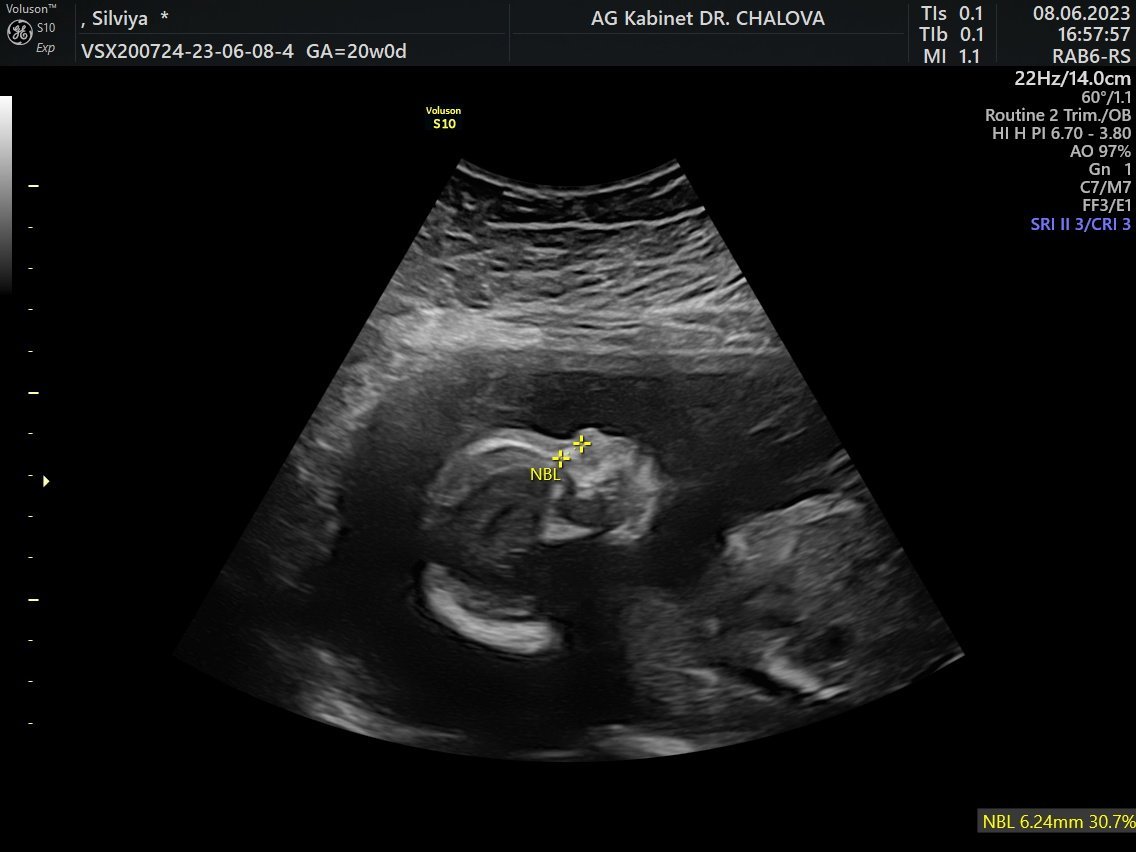

Момичетааа, може ли да покажете ако имате снимки на бебчовците в профил? Нещо моето ми се струва, че не му е наред, нищо че докторът каза,че си е добре. Аз ли откачам, не знам, но тоя профил на носа и устните нещо ме притеснява.

Ето го нашият мъник,незнам какво точно те притеснявам щом лекаря ти е казал,че всичко е наред.

Вашето носле е по-мъничко и сладко сякаш, ама муцунката и тя е малко изтумбена. Абе не мога да обясня...